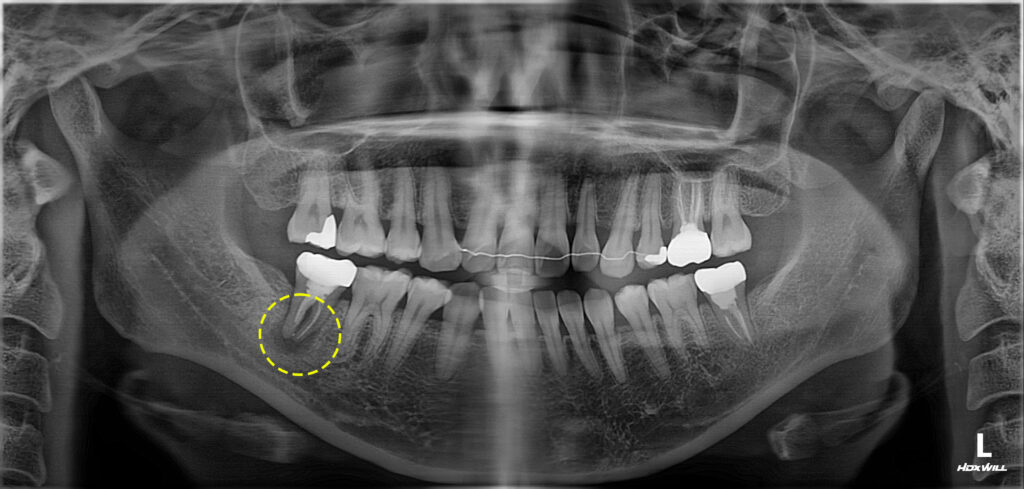

치료 중에도 볼 쪽으로 부어 있던 부종이

가라 앉지 않아서 치아 재식술을 시행하기로

잠정 결정 후 1달간 환자분의 여행 일정으로 인해

치료를 진행하지 못했습니다.

1달 후 부종이 사라지고 치근단 병소가

해소되어 최종보철물 제작을 진행하였습니다.

이후에도 점차 골소실이 메워져 수술 없이

마무리가 되었습니다.